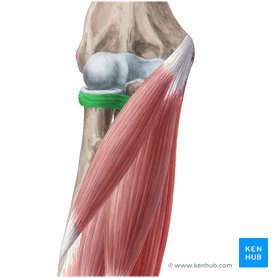

what type of joint is highlighted?

pivot

saddle

condyloid

hinge

ball and socket

what type of joint is highlighted?

pivot: annular ligament = creates pivot joint !!

saddle

condyloid

hinge

ball and socket